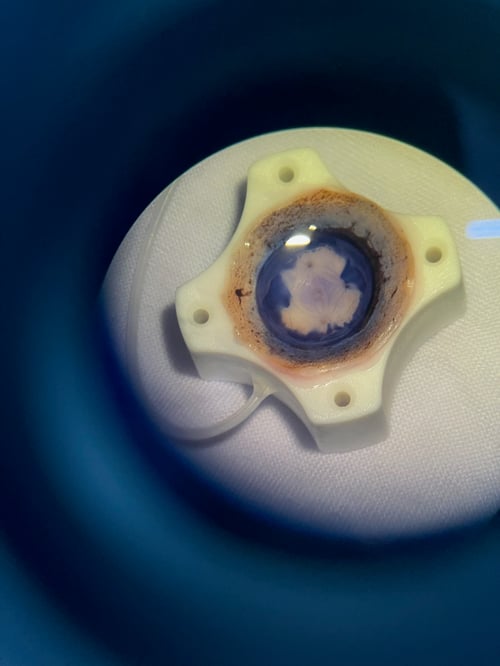

Michael’s first stop was in Ho Chi Minh City, Vietnam where he worked closely with the Ho Chi Minh City Eye Hospital. This was an extension of the endothelial keratoplasty (EK) skills transfer courses led by Dr. Anthony Aldave of Visionaries International, who has been teaching Vietnamese surgeons advanced transplant techniques, specifically DSAEK and DMEK, throughout his career.

Eversight provided 16 surgical corneas, four PKP, eight DSAEK and four DMEK, and an additional 20 training corneas to practice donor tissue preparation for DMEK.

“One of the main challenges in Vietnam is the lack of locally available tissue, making it difficult for surgeons to perform these life-changing procedures,” Michael said. “To address this gap, we conducted two DMEK preparation wet labs, training four surgeons on preparing the grafts themselves. This skill is essential for the region as there is no sustainable access to DMEK-prepared tissue, forcing local surgeons to rely on whole corneas.”

“Our goal was to train a technician to prepare DMEK tissue, a process not yet adopted in Thailand,” Michael said. “Currently, Thai surgeons prepare tissue for DMEK surgery themselves, which is not sustainable due to the time needed and the risk for damaging the tissue.”